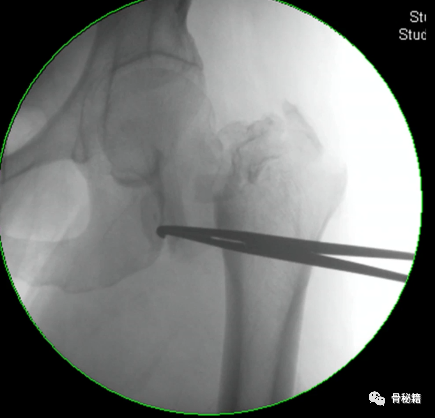

5、钉子的深度。逆行髓内钉的最佳深度是布鲁门萨线的顶点位置,正位居中

近端一般是小粗隆水平以上

6最后提一点锁钉的小技巧,不要造成主任打主钉5分钟,我们锁钉2小时。我们透视的时候,要把锁定空透成两个圆形,但是在操作中往往是椭圆形,这个时候根据椭圆形的长轴来方向来移动C臂,就可以透一个好的圆形了,在此情况下完成锁钉就相对容易些。